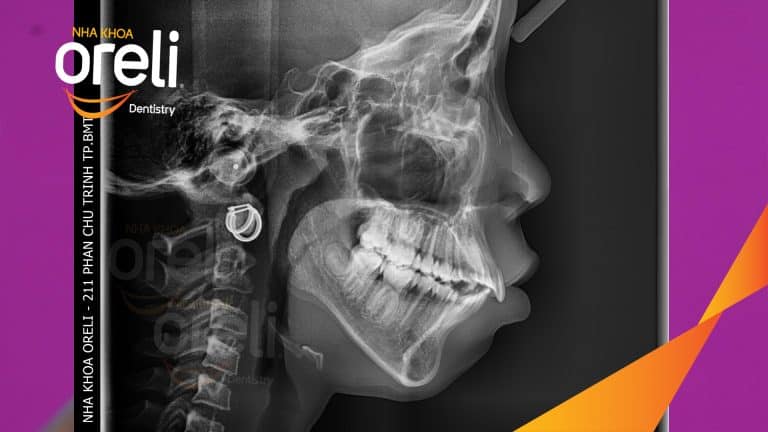

Ca niềng chỉnh hô nhổ 2 răng 4 hàm trên di gần răng 7 8 hàm dưới cho nụ cười đẹp – Kết quả sau hơn 2 năm ở Oreli Niềng răngDi gần răng 7 8Hô Xem thêm